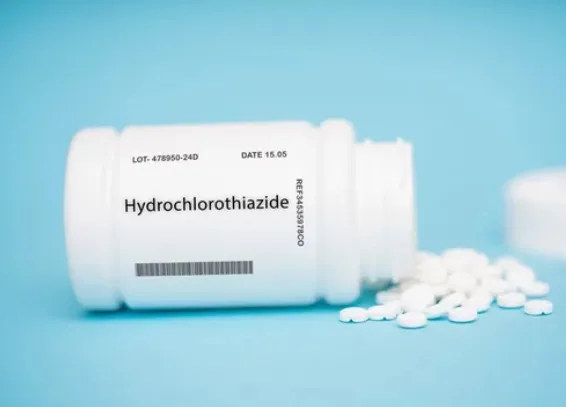

Resistência a diuréticos na insuficiência cardíaca: aumentar o diurético de alça ou associar tiazídico?

Resistência a diuréticos na insuficiência cardíaca: aumentar o diurético de alça ou associar tiazídico?